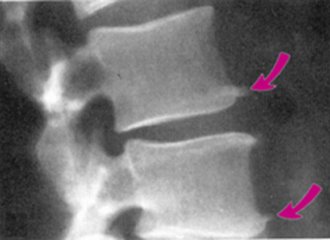

前面我们也介绍过骨刺的发生原因和产生机理。骨刺(骨赘)是人的机体对于应力、磨损、炎症等的一种反应,通过这种适应性反应,能够起到稳定局部环境,维持机体的功能,从这个角度上说,骨刺是一种正常的代偿反应,并非多余。

虽然骨刺是医生诊断骨性关节炎的一个依据,但绝大多数不是引起局部疼痛的真正原因,更不是它直接引起疼痛症状。只有当局部的骨刺对周围的软组织产生顶压等刺激时,才会引起局部的疼痛症状,并且这种情况非常少见。

导致关节疼痛的主要原因是关节软骨损伤、半月板磨损、关节力线改变等。因而相应的治疗需要在准确把握病因的基础上治疗才是正确的选择。